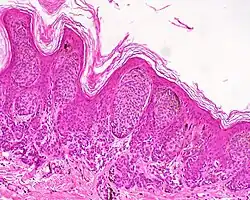

Lentiginous melanocytic naevus

A melanocytic nevus (also known as nevocytic nevus, nevus-cell nevus, and commonly as a mole)[1][2] is a usually noncancerous condition of pigment-producing skin cells. It is a type of melanocytic tumor that contains nevus cells.[2] A mole can be either subdermal (under the skin) or a pigmented growth on the skin, formed mostly of a type of cell known as a melanocyte. The high concentration of the body's pigmenting agent, melanin, is responsible for their dark color. Moles are a member of the family of skin lesions known as nevi (singular "nevus"), occurring commonly in humans.[3][4] Some sources equate the term "mole" with "melanocytic nevus",[2] but there are also sources that equate the term "mole" with any nevus form.[3]